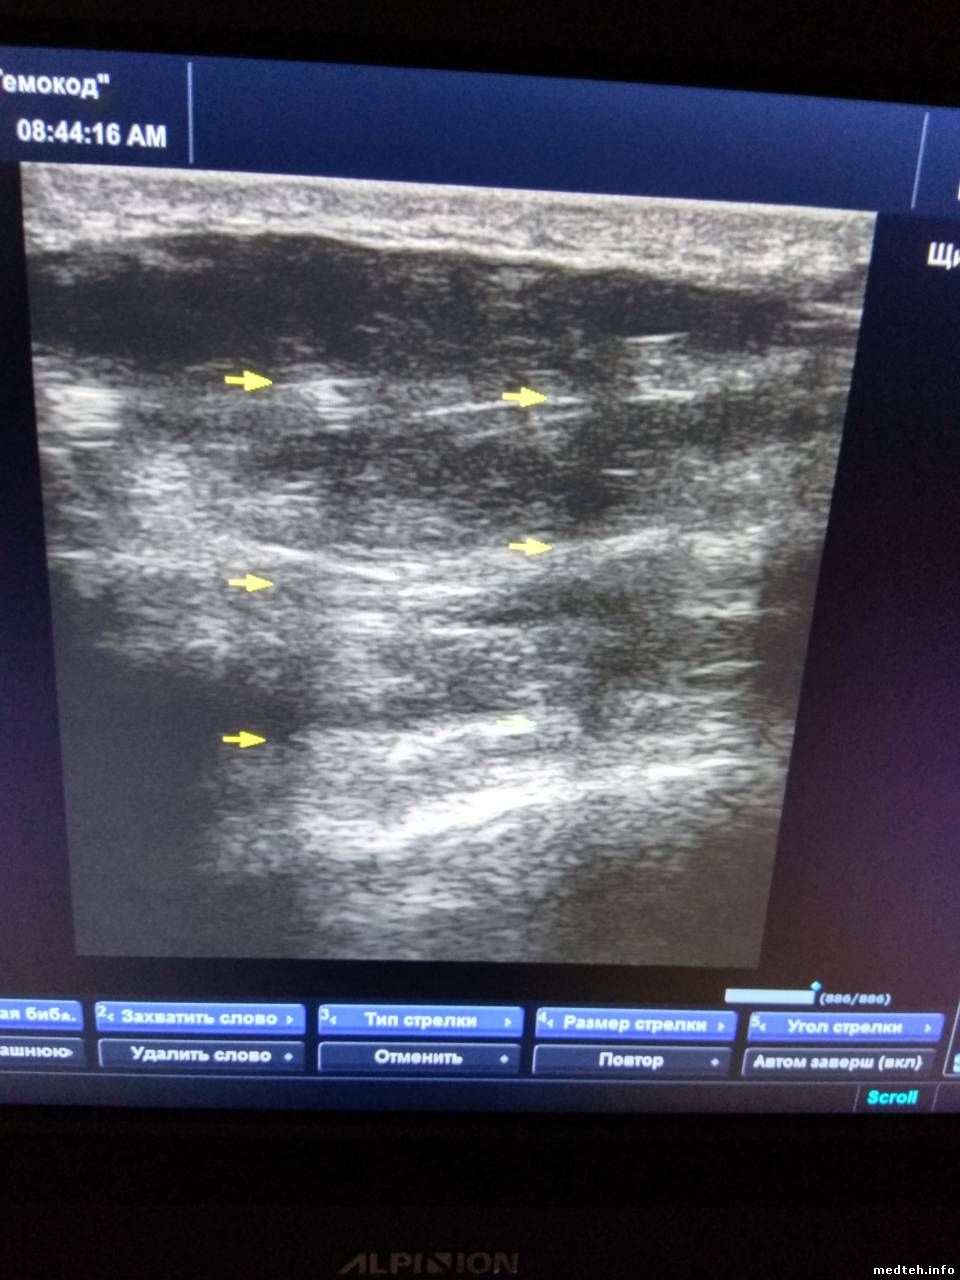

Добрый день! Уважаемые коллеги, посоветуйте,плиз..Что можно сделать в данной ситуации? Замена линзы? И если исправит проблему, то кто может взяться за это? Соответственно, сроки ремонта,цена,гарантия на работу? Сам ни разу такое не делал и опасаюсь...

Фото прилагаю..

2007676.jpg (50.8 Kb) · 1106821.jpg (50.8 Kb) · 6863907.jpg (127.3 Kb) · 2895305.jpg (127.3 Kb) · 5262964.jpg (88.9 Kb) · 5110581.jpg (62.2 Kb)

pilot9275Дата: Пятница, 15.Фев.2019, 09:36 | Сообщение # 432

Чебоксары

женек 75

Сделали быстро но качество посмотрите сами на фото.

3734761.jpg (109.2 Kb)